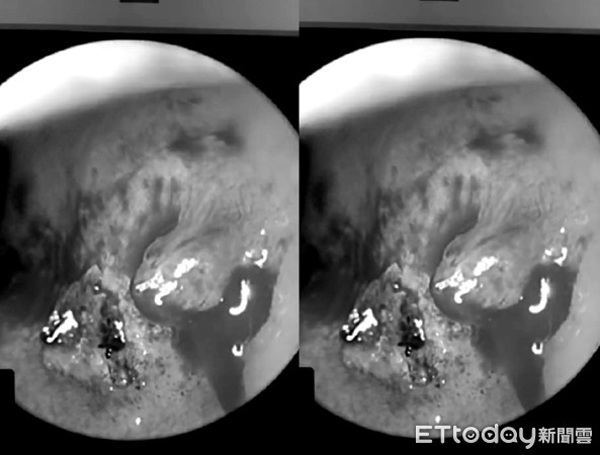

Một người đàn ông 24 tuổi ở Đài Trung, Đài Loan được bạn gái đưa tới viện cấp cứu vào đêm khuya, anh ta kêu bị chảy máu cam liên tục, dù đã dùng giấy chặn lại nhưng vẫn không ngừng chảy. Qua nội soi, bác sĩ nhận thấy mạch máu bị đứt cần vào phòng mổ phẫu thuật laser để cầm máu.

Cứ khi nào quan hệ tình dục với bạn gái, chàng trai trẻ sẽ bị chảy máu mũi. (Ảnh minh họa)

Bác sĩ khuyến cáo nếu các thao tác cầm máu lặp đi lặp lại hai lần đều vô ích, bạn nên đi khám càng sớm càng tốt. (Ảnh minh họa)